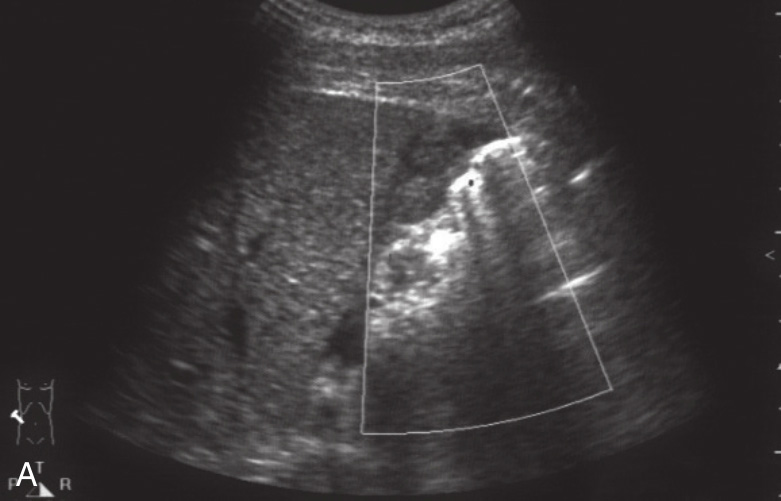

图1-12-2 真性肝破裂灰阶超声图像

A.肝右叶片状低回声区,其内血流信号不明显;B.盆腔少量积液